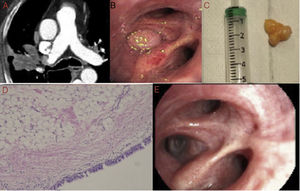

We report the case of a 69-year-old man with a history of alveolar infiltrate in the right upper lobe, without radiological resolution despite the administration of empirical antibiotic treatment. Computed tomography (CT) showed a lesion of fat density (−100 UH) located in the anterior segmental bronchus (corresponding to B3) extending to subsegmental bronchi B3A and B3B (Fig. 1A). The lesion was subsequently confirmed with flexible bronchoscopy (Fig. 1B). It was completely resected under general anesthesia with laryngeal mask, using the Pentax Medical EB19-J10® flexible bronchoscope and ERBE® cryotherapy probe (2.4mm diameter). There were no complications during the procedure.

(A) Lesion of fat density in the chest CT scan in the anterior segmental bronchus of the right upper lobe. (B) Examination with flexible fiberoptic bronchoscopy, showing the lesion occupying the entrance to anterior segmental bronchus of the right upper lobe. (C) Image of the lesion after excision. (D) Histologic image of the lesion (×10). (E) Image of recanalization of anterior segmental bronchus of the right upper lobe after treatment.

The pathology report characterized the lesion as an endobronchial lipoma, a rare benign entity (incidence of 0.5%),1 with a clinical progress that in most cases is insidious (hemoptysis, dyspnea, cough, etc.) or silent (Fig. 1C and D). Surgical intervention has now been relegated to the background as a result of advances in respiratory endoscopy, a procedure that is less invasive and relatively free of complications.2